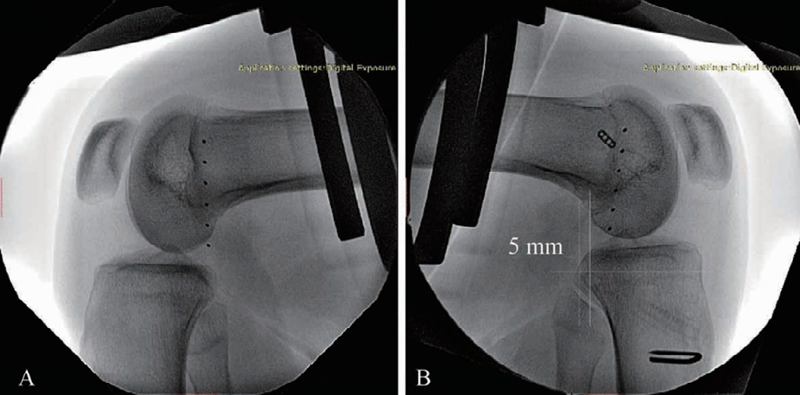

后方应力位或跪位X线检查是诊断PCL损伤的可靠方法(图6),对比健侧,后移增加0~7mm为PCL部分损伤(图7),8~11mm为单纯PCL全部断裂(图8),12mm以上可能为PCL和PLC等其他结构合并损伤(图9)。

图7 PCL部分损伤X线影像

应力位X线片(B)示胫骨后移超过健侧(A)5mm

图8 PCL完全断裂X线影像

应力位X线片示患侧(B)胫骨后移超过健侧(A)10.1mm